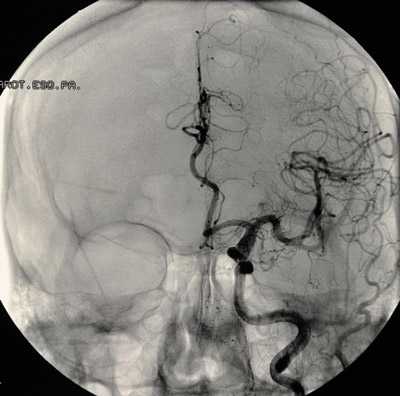

Для остановки кровотечения при интраоперационном разрыве аневризме могут быть использованы прямые и непрямые методы гемостаза. К прямым методам гемостаза относят клипирование аневризмы, закрытие дефекта её стенки при помощи биполярной коагуляции и тампонирование дефекта кусочком марли или фрагментом мышцы, к непрямым методам — глубокую артериальную гипотензию, временное клипирование (ВК) несущего аневризму сосуда и метод внутрисосудистой баллон-окклюзии и аспирации крови.

Выбор метода гемостаза осуществляется в зависимости от времени возникновения кровотечения и его интенсивности. При возникновении внеконтактных интраоперационных разрывов аневризмы на ранних этапах операции можно прибегнуть к двум основным методам — сдавлению общей или внутренней сонной артерии на шее и к индуцированной артериальной гипотензии.

В последние годы в качестве ассистирующей методики нашел свое место метод эндовазальной окклюзии церебральных сосудов, при помощи которого в случае интраоперационных разрывов аневризмы удается контролировать кровотечение. Однако данный метод доступен только в клиниках, имеющих соответствующее оснащение.

При кровотечениях, возникающих на основных этапах операции и имеющих небольшую интенсивность, следует отдавать предпочтение прямым методам гемостаза. При невозможности остановить кровотечение прибегают к методам, снижающим локальное АД (в бассейне несущей аневризму артерии) — временное клипирование несущей артерии и внутрисосудистой баллон-окклюзии. При сильном кровотечении, остановить которое не удается перечисленными способами, средства гемостаза могут быть дополнены индуцированной артериальной гипотензией.

При распространении дефекта стенки аневризмы на стенку несущего её сосуда выполняют треппинг (наложение постоянного клипса на несущую аневризму артерию) или производят пластику образовавшегося дефекта стенки сосуда. Учитывая тяжелые ишемические осложнения треппинга, его выполняют при невозможности остановить кровотечение всеми перечисленными выше способами.